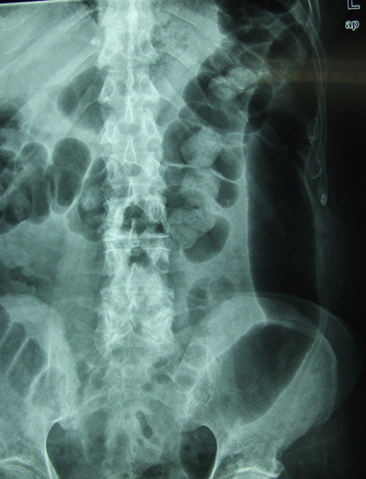

Escoliosis. Espondilolistesis.